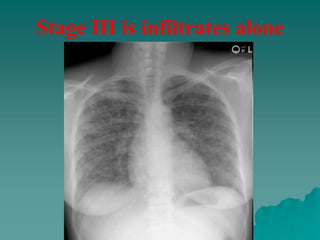

– stage 3, infiltration alone.

Stage III is infiltrates alone